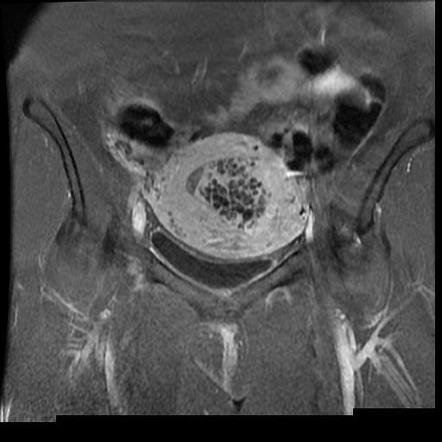

Hydatidiform Mole Mri

Complete hydatidiform mole | Radiology Reference Article | Radiopaedia.org Invasive mole | Radiology Reference Article | Radiopaedia.org Molar pregnancy | Radiology Reference Article | Radiopaedia.org Molar pregnancy | Radiology Reference Article | Radiopaedia.org | Hydatidiform Mole Mri